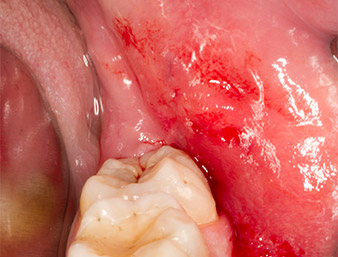

The wound healed without complications (Fig. 17) and the sutures were removed after seven days. The patient reported the return of proper sensitivity. There was no longer any pain.

Condition after removal of sutures

Fig. 17: Condition after removal of sutures 7 days after extraction: Wound healing progresses without complications. Paraesthesia, present after the initial osteotomy, has healed; pain no longer present.